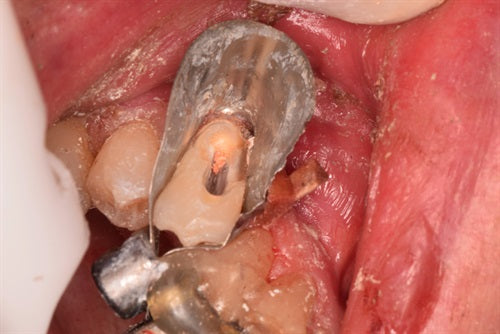

Let's violate biologic width and see what happens

#18 has deep cervical decay at the distal Step 1 Patients chief complaint was food impaction. All decay has been removed Step 2 DL margin was flush with the bone... Read More